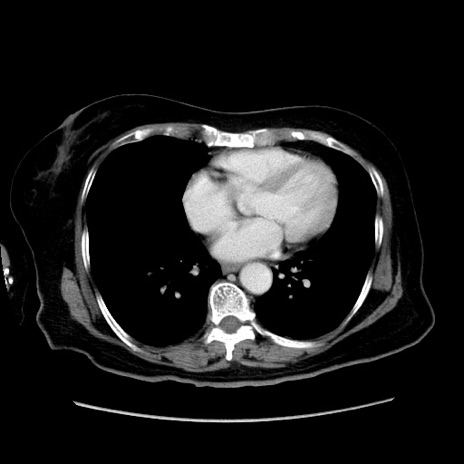

症例19(横断像)

【症例】80歳代女性

【主訴】下腹部痛

【現病歴】約8時間前より下腹部痛の出現あり、救急外来受診。

【既往歴】両側付属器切除

【身体所見】意識清明、下腹部正中に手術痕あり、その部位に一致して圧痛と反跳痛あり。腸蠕動音は亢進。

【データ】WBC 9300、CRP 0.15